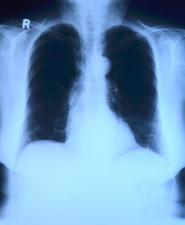

1875 rok jest uznawany za początek tomografii komputerowej. Rok ten był przełomowy dla dziejów medycyny ze względu na wielkie odkrycie Wilhelma Conrada Rentgena. Przedmiotem jego badań były różnego rodzaju promieniowania. Dzięki jego pracy zostało odkryte promieniowanie rentgenowskie. Uhonorowaniem jego dorobku naukowego było przyznanie w 1901 roku nagrody Nobla w dziedzinie fizyki.

Pierwsze zdjęcie wykonane za pomocą promienia rentgenowskiego zostało wykonane na żonie odkrywcy, a dokładnie na jej ręce. Wydarzenie to zapoczątkowało rozwój diagnostyki kostnej i płucnej. Kolejnym krokiem w pracy odkrywcy było doskonalenie i rozwój technik radiologicznych. W efekcie doprowadziło to do powstania pierwszego urządzenia służącego do tomografii komputerowej.